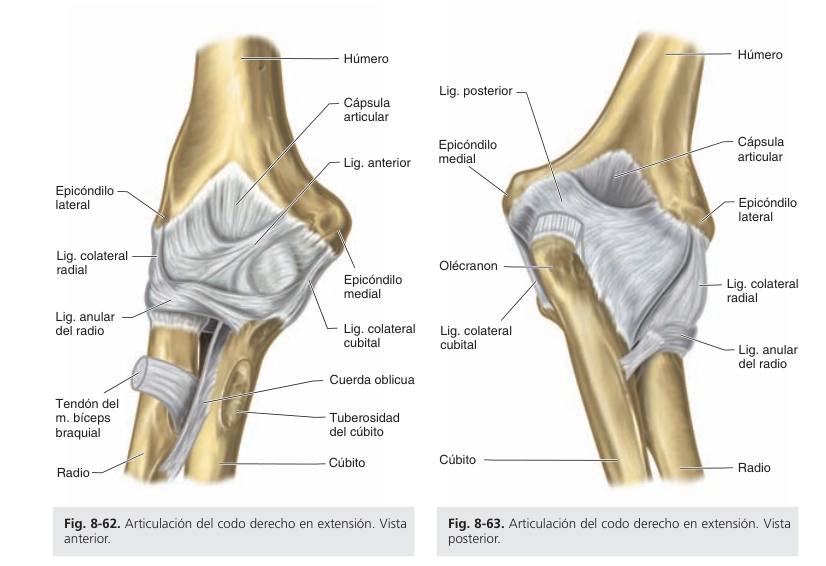

Codo: ligamentos

¿Cuáles son los ligamentos principales del codo?

Ligamento Colateral Ulnar (Medial): Está compuesto por 3 fascículos (anterior, medio y posterior). Desde el epicóndilo medial hacia la ulna (A y M → Apf. Coronoides, P → Borde de Olécranon) Reforzado por ligamento de Cooper. Su función principal es resistir el estrés en valgo.

• Ligamento Colateral Radial (Lateral): También está compuesto por 3 fascículos (anterior, medio y posterior). Desde el epicóndilo lateral hacia abajo, donde se mezcla con el ligamento anular. (A y M → Escotadura radial, P → Borde de Olécranon) Su función principal es resistir el estrés en varo.

• Ligamento Anular del Radio: Rodea la cabeza del radio manteniéndola fija en la escotadura radial de la ulna. Su función es permitir la rotación sin luxación.

• Ligamento Cuadrado (de Dénucé): Desde el borde inferior de la escotadura radial hacia el cuello del radio. Actúa como refuerzo inferior de la articulación radioulnar.

• Ligamento Anterior: Desde la cara anterior de los epicóndilos, fosa coronoidea y fosa radial hacia la apófisis coronoides y el ligamento anular. Contiene fibras oblicuas (laterales y mediales) que se dirigen desde sus respectivos epicóndilos hacia el centro.

• Ligamento Posterior: Desde la fosa olecraniana hacia el olécranon. Está formado por fibras transversales (ubicadas por encima del olécranon) y fibras oblicuas (que van desde los bordes medial y lateral de la fosa hacia los respectivos bordes del olécranon).